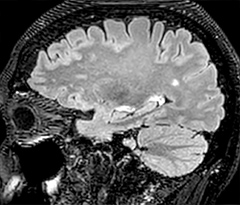

Fast MS protocol with optional sequences

The abbreviated MS protocol for brain is only around 9 minutes, so in case of suspected multiple sclerosis, one or two more advanced sequences may be added, such as PSIR (phase sensitive inversion recovery) or susceptibility-weighted sequences to help us make more confident diagnoses in these inflammatory cases.

In this example, the optional 3D multishot susceptibility weighted sequence with 0.6 mm isotropic voxels is 2 lesions with a central vein sign (arrows) and one lesion with a phase-rim sign (arrowhead). The total scan time, including SmartBrain and axial PD/T2 3mm, is 11:10 min. and is 18:30 min. with the optional 3D PSIR and 3D SWI multishot included.

“In multiple sclerosis patients, we increasingly include a multishot susceptibility sequence [3] in our routine cases, thanks to the shorter scan times. Our abbreviated MS protocol for brain is around 8 to 9 minutes, so we can ask for one or two additional sequences to visualize the central veins, or to get an additional contrast to better depict posterior fossa lesions. In cases of white matter lesions of unknown significance on FLAIR images, for example when we see high signal hyperintensities in the brain, we can add on more advanced sequences such as PSIR (phase sensitive inversion recovery) or susceptibility-weighted sequences to help us in distinguishing between MS and nonspecific or vascular abnormalities in these inflammatory cases.”